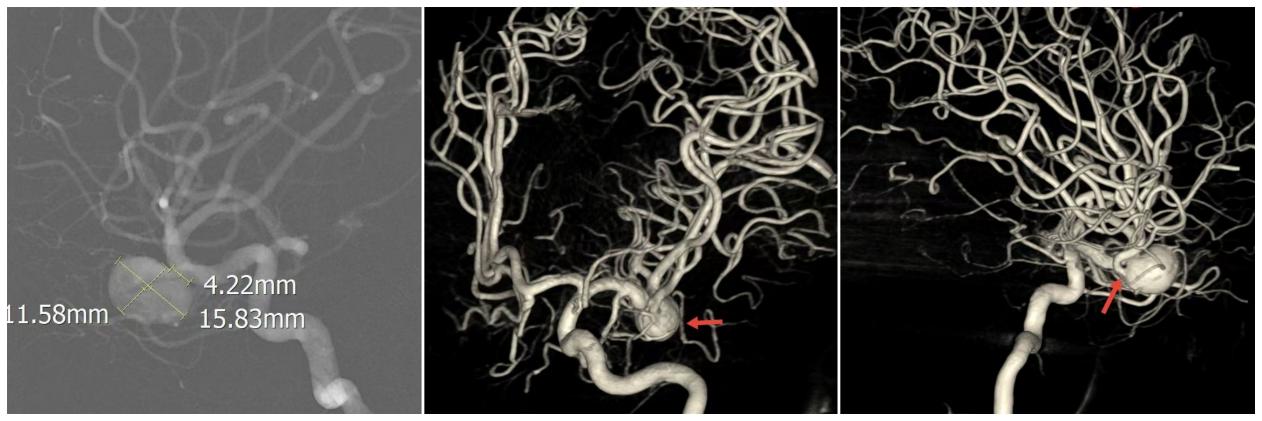

患者男性,40岁,因头痛多年于外院检查发现右侧大脑中动脉瘤,既往有糖尿病史及头部外伤史。入院查体神经系统无阳性体征。入院后行全脑血管造影检查提示右侧大脑中动脉M1段分叉处宽颈动脉瘤,椭圆形,大小约15.8*11.6mm,瘤颈宽约4.2mm,下干自动脉瘤上发出。动脉期可见动脉瘤内明显的涡流。

▲动脉瘤位于右侧大脑中动脉M1段分叉处,椭圆形,大小约15.8*11.6mm,瘤颈宽约4.2mm,下干自动脉瘤上发出。

▲密网支架打开形态良好,贴壁满意,术后即刻造影见动脉瘤内造影剂滞留,体积明显缩小,且下干血流通畅。